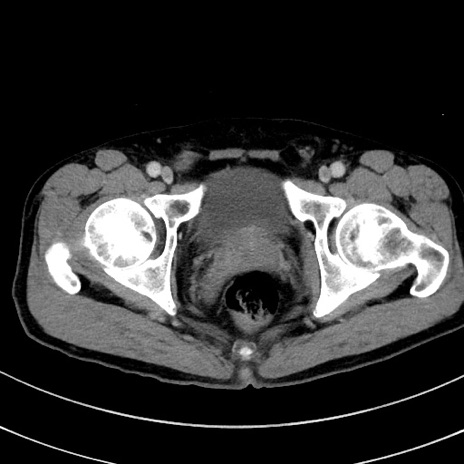

症例8(横断像)

【症例】 60歳代男性

【主訴】 黒色吐物

【現病歴】 4日前から嘔気自覚、2日前の朝食後にも嘔気あり、自分で手で嘔吐反射起こし嘔吐したところ血が混ざっていたため受診。

【既往歴】 5年前汎発性腹膜炎を伴う急性虫垂炎で手術、高血圧、前立腺肥大症、高脂血症

【身体所見】 腹部正中に手術癩痕あり 腹部平坦・軟圧痛なし膨満感あり

【データ】WBC 8400、CRP 4.54